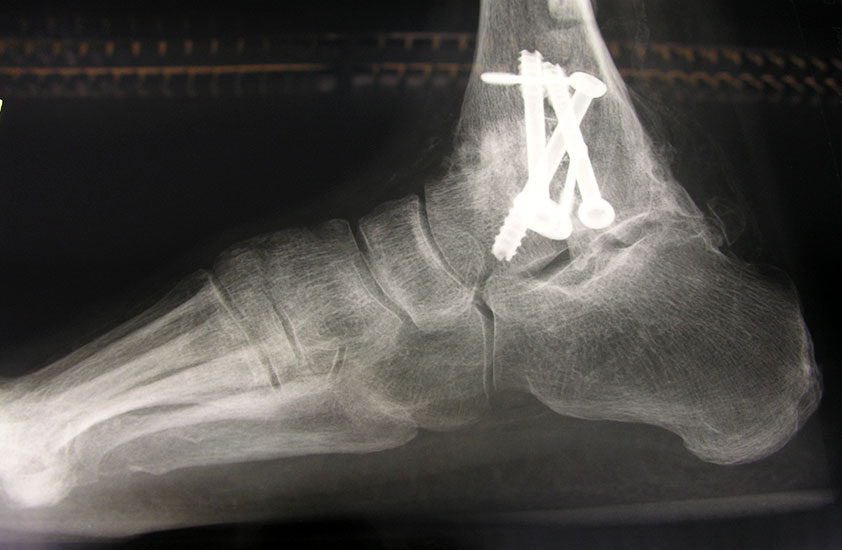

Fixation mit mindestens 2, ggf. 3 kanülierten Schrauben (6,0, 6,5 oder 7,0 mm), die von medial-kranial und lateral-kranial nach kaudal oder von anterior-kranial nach posterior-distal (Abb. 6) in den Talus unter BV-Kontrolle in 2 Ebenen eingebracht werden (Sabo 2014). Im amerikanischen Sprachraum ist die Verwendung der von dorsal-lateral paraachillär nach anterior-medial in den Corpus tali gerichteten Zugschraube geläufig („home run-screw“) (Abb. 7). Es ist darauf zu achten, das untere Sprunggelenk nicht mit Schrauben zu perforieren. Idealerweise spannen die Kompressionsschrauben, deren Gewindegänge nur im Talus liegen sollten diesen stabil in die Malleolengabel ein.

Abbildung 6

Abbildung 7